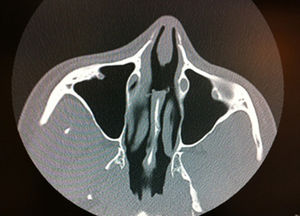

La paciente fue valorada por el servicio de otorrinolaringología (ORL) sin hallar anomalías en los estudios realizados: analítica sanguínea incluyendo serología luética, ECA, ANA, anti-DNA, c-ANCA y p-ANCA; determinación de tóxicos de orina y cultivos bacterianos sin gérmenes patológicos. Mediante rinoscopia se observaba una perforación septal de bordes cruentos. La TAC permitió visualizar la perforación septal sin evidencia de enfermedad en los senos ni en las demás estructuras óseas (fig. 1). Se practicaron 6 biopsias en sacabocados evidenciando una mucosa ulcerada con fibrosis e inflamación del corion, en ausencia de fenómenos de vasculitis, trombosis, granulomas ni atipia (fig. 2). En servicios de ORL se pautó, durante 18 meses, tratamiento con antibióticos tópicos y orales con escasa mejoría, y posteriormente, le fue implantado un botón septal que fue retirado a los 15 días por intolerancia de la paciente.